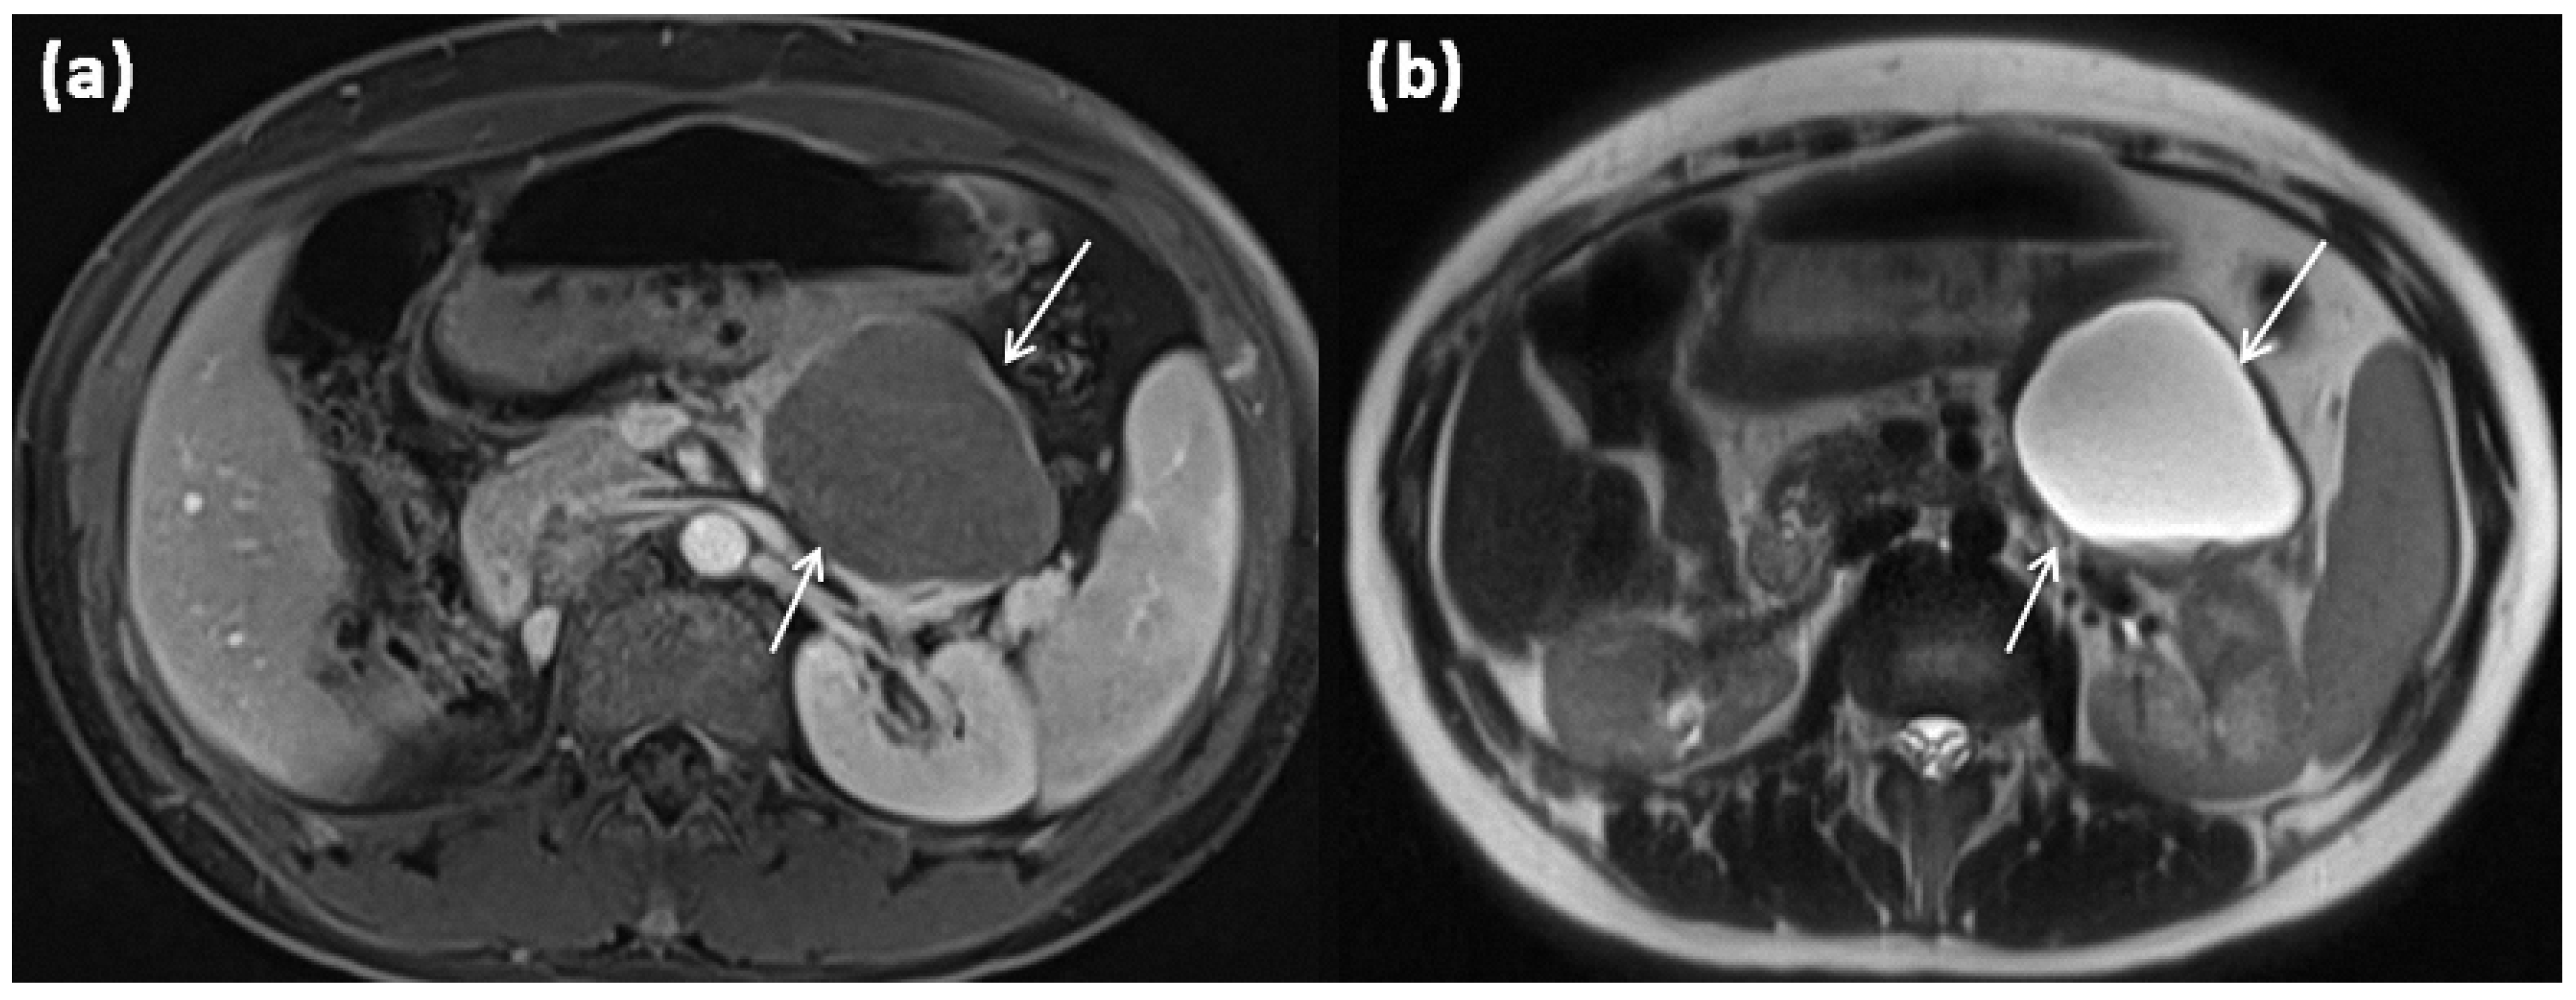

3.2. Macrocystic Tumors: Mucinous Cystic Neoplasms (MCN)

MCNs account for approximately 10% of cystic pancreatic tumors []. Mucinous cystic neoplasms in this context are solitary, well-circumscribed space-occupying lesions with smooth surfaces and septations, which appear monocystic or oligocystic and have a rather strong wall (Figure 5) [,]. The cyst content is mucinous and rich in diagnostically useful CEA and CA 19-9 []. In histopathology, ovarian stroma is typically found in MCN [,], which explains its almost exclusive occurrence in premenopausal women (Figure 6).

Size can vary widely, single sizes up to 35 cm have been described, with sizes greater than 10 cm being rare []. Surrounding the MCN is a fibrous pseudocapsule of variable thickness. In 95% of cases, the tumors are localized in the pancreatic body and pancreatic tail [,,,].

The often thick cyst walls are well-demarcated in any cross-sectional imaging. MRI usually shows a macrocystic mass, which is usually composed of individual parts often exceeding 2 cm []. The cyst content, typically with a T2w hyperintense signal, may be aqueous, but may likewise be hemorrhagic or have varying protein concentrations with varying degrees of thickening. Therefore, in CT, higher HU values, and in MRI, the variability of native T1 and T2 signals, can be observed. After contrast application, an enhancement of the cyst wall, as well as of the septations, is seen []. In this context, especially in dynamic MRI sequences, an enhancement can be observed, particularly in the later phases due to the fibrous cyst walls; in addition, small mural nodules are possible [,,]. MRCP is mainly used for the differential diagnostic exclusion of a ductal connection, which is not present in MCN.

Peripheral eggshell-like calcifications, which are described as pathognomonic, are rare overall [], but are easier to detect using CT and are considered to be a criterion for a potentially malignant transformation, especially in the case of new occurrence or particularly strong or widely peripheral manifestation []. An occurrence at an older age is suspicious for malignancy as well as large individual cysts of more than 6 cm and irregular and very thick cyst walls with papillary projections in the sense of solid nodular components or hypervascular areas [,,,].

The guidelines recommend surgical resection for MCN ≥ 40 mm, and also for symptomatic MCN or morphologic signs of malignancy, it is then recommended regardless of their size (grade IB recommendation) []. Cytologic workup by fine needle aspiration is recommended only if imaging is unclear and no differentiation between mucinous vs. non-mucinous neoplasm can be made (grade II C recommendation). Malignant potential can be determined this way [].